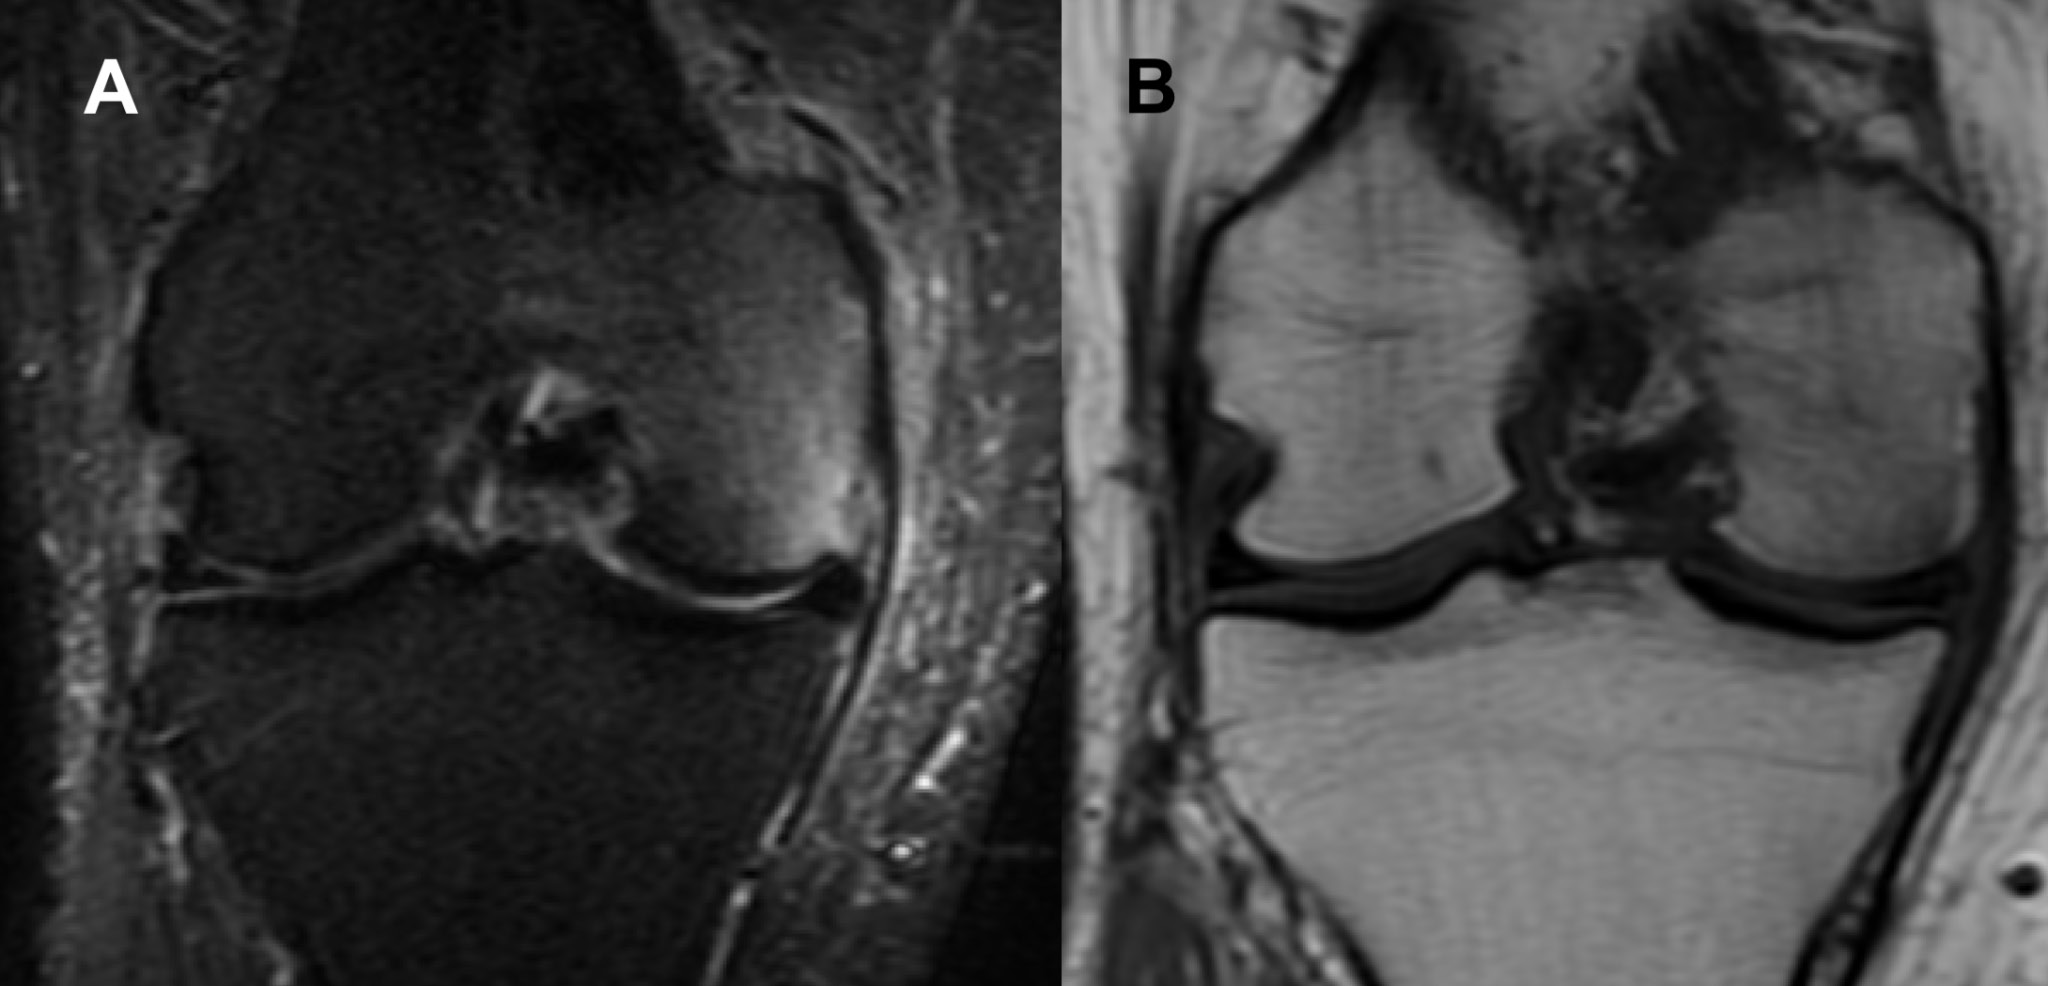

On clinical examination, the patient had a full range of motion and a stable knee joint. The patient experienced pain during extension and near-full extension. Palpation of the MFC and medial joint space revealed local tenderness. Additionally, the patient experienced pain when varus stress was applied to the knee in 10° knee flexion. An MRI of the patient’s right knee was performed immediately following the orthopedic appointment (7 weeks after the onset of knee symptoms). Magnetic resonance imaging in short tau inversion recovery (STIR) sequence revealed a large area of diffuse increased signal in the MFC and the medial aspect of the intercondylar region (Figure 1).

Fig. 1. Magnetic resonance imaging (MRI) coronal view of the right knee (Case 1) performed in the symptomatic period. There is diffuse increase in signal in the medial femoral condyle in both (A) short tau inversion recovery (STIR) fast spin echo (FSE) and (B) proton density (PD) sequences. It is noteworthy that the signal intensity in the subchondral bone is only slightly affected in the (B) PD sequence. Edema of the soft tissues on the medial side of the joint is also clearly visible